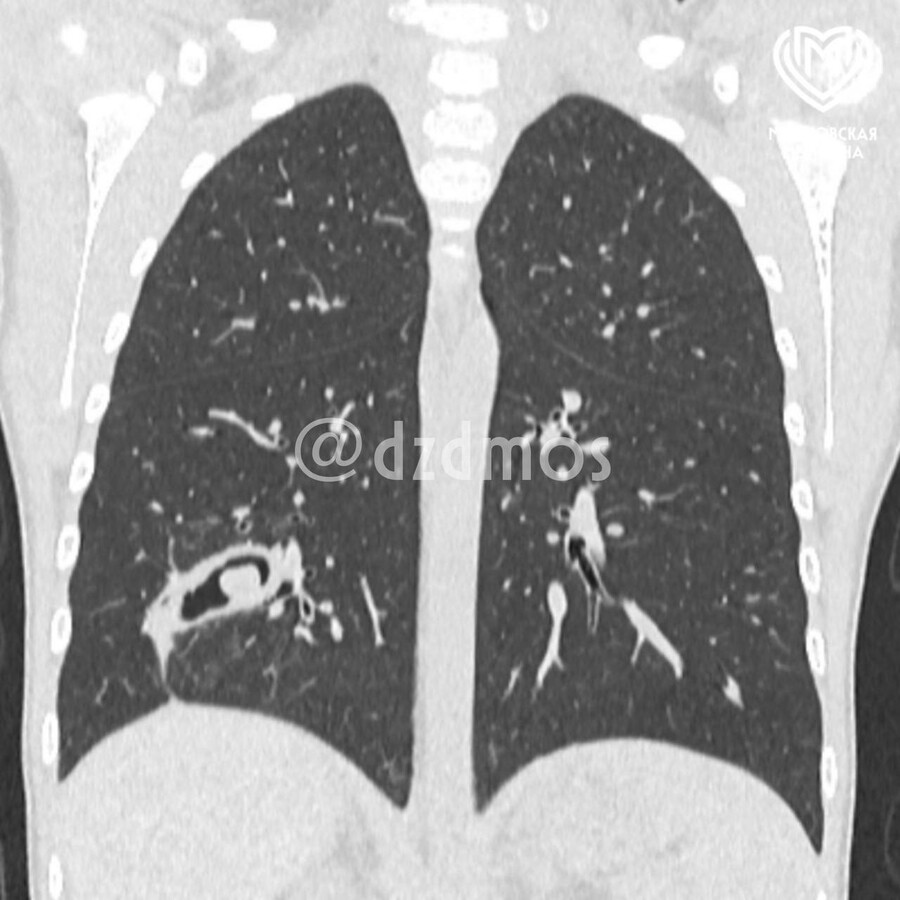

«Врачи провели обследование и на КТ увидели серьезные видоизменения в бронхах. Это было инородное тело в дыхательных путях справа, которое угрожало здоровью девочки. Как выяснилось, часть скорлупы семечки глубоко впаялась в третий субсегмент правого легкого, из-за чего у пациентки образовался бронхоэктаз, то есть плохо функционировали из-за скопления гноя бронхи», — рассказал Дмитрий Еремин, детский хирург, заместитель главного врача по хирургической помощи.